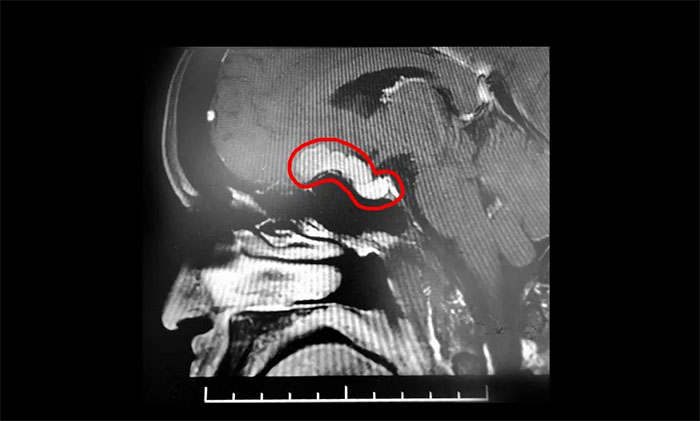

入院检查显示,左眼视力下降,外侧视野缺损。鞍区MRI平扫+增强显示,鞍上可见类椭圆形异常信号,大小约2.8cm*1.5cm,与垂体分解分界清晰,与视交叉、海绵窦分界欠清晰。

▲ 肿瘤向鞍上生长